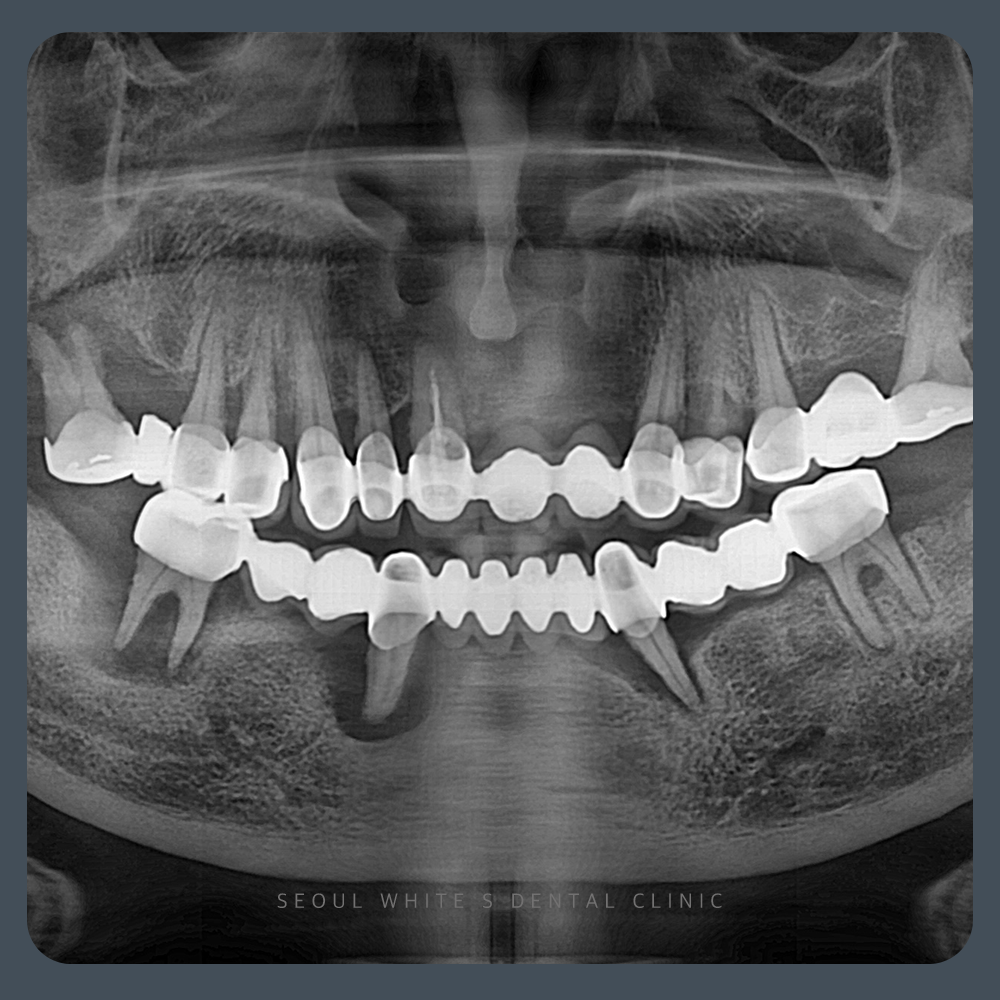

2021.12.28

내원 시점에서 이미 상·하악에 다수의 골소실이 관찰되었으며, 특히 하악은 전체적으로 치아의 동요도가 심각했습니다. 일부 치아는 치주 인대가 확장되고, 치근 분지부(furcation) 병소까지 열려 발치를 피할 수 없는 상태였습니다.

이전 치료에서 문제가 된 보철을 조기에 관리했다면 일부 치아는 지킬 수 있었을지도 모르지만, 내원 당시에는 이미 하악 치아를 보존하기 어려운 상황이었습니다.

하악의 경우 브릿지를 지탱하던 모든 치아를 발치하고 골이식을 진행하기로 결정했습니다. 다만, 브릿지가 있던 자리를 제외한 나머지 부위는 골 상태가 양호하여 발치·골이식 후 안정화 기간을 거치면 충분히 회복 가능하다고 판단했습니다. 상악에서는 일부 치아가 늦지 않게 발견되어 보존할 수 있었고, 발치가 불가피한 부위에는 골이식을 병행했습니다.